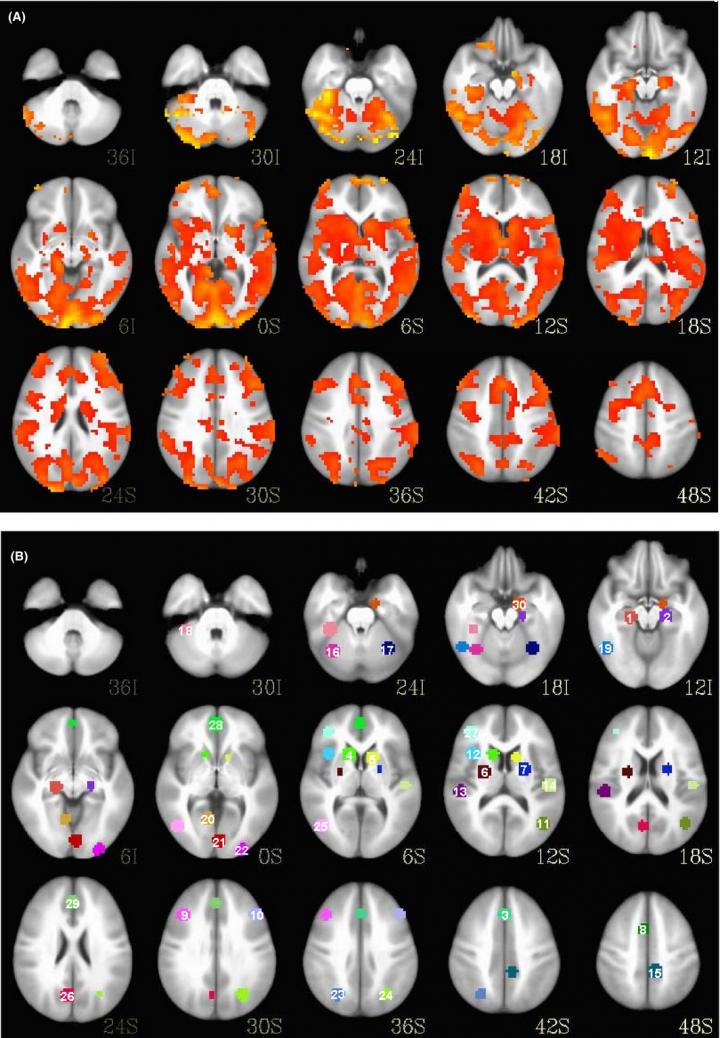

The algorithm used an analysis of two types of patient brain scans, among other data, to predict with 100 percent accuracy which patients responded well and which didn't. And the algorithm also predicted the reductions in symptoms at eight weeks, an achievement made even more impressive by the fact that only objective biological data were used for prediction rather than subjective opinions from experienced physicians.